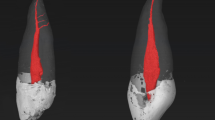

Table 1 shows the mean of slices presenting microcracks, taking into account all evaluated samples. These results indicate a low percentage of microcracks before preparation, being similar between groups (P > 0.05). The enlargement of apical foramina caused new microcracks with a higher percentage when compared to the preparation 1 mm short of apical foramen (P < 0.05). New microcracks were not found in the control group (P > 0.05). Figure 1 shows the appearance of new microcracks only after foraminal enlargement, as this finding was not detected in the control group.

Figure 2 indicates significant higher apical transportation after foramen enlargement in comparison with the control group (P < 0.05). Figure 3 shows the presence of microcracks and apical deformations in 3D reconstructed images of nano-CT.

The foraminal enlargement caused more transportation in the root apex than the instrumentation performed 1 mm short of apical foramen. Reciproc Blue files are submitted to a heat treatment that improves their flexibility31, making them suitable for instrumentation of curved root canal32. However, previous studies have shown some transportation, even using instruments with heat treatment8,33. Some authors have also pointed out that this transportation can occur more frequently in preparations 1 mm beyond the foramen8,34. Root canal transportation may negatively affect the outcomes of endodontic treatments35, especially in the apical region that represents a critical zone to maintain infection of the root canal system36. In addition, as can been observed in Fig. 3, the transportation is still associated with deformations of the apical foramen8. In agreement, a previous study also observed higher apical foramen deformations after foraminal enlargement34. Moreover, it should be emphasized that such deformations may affect the sealing of the root canal filling.